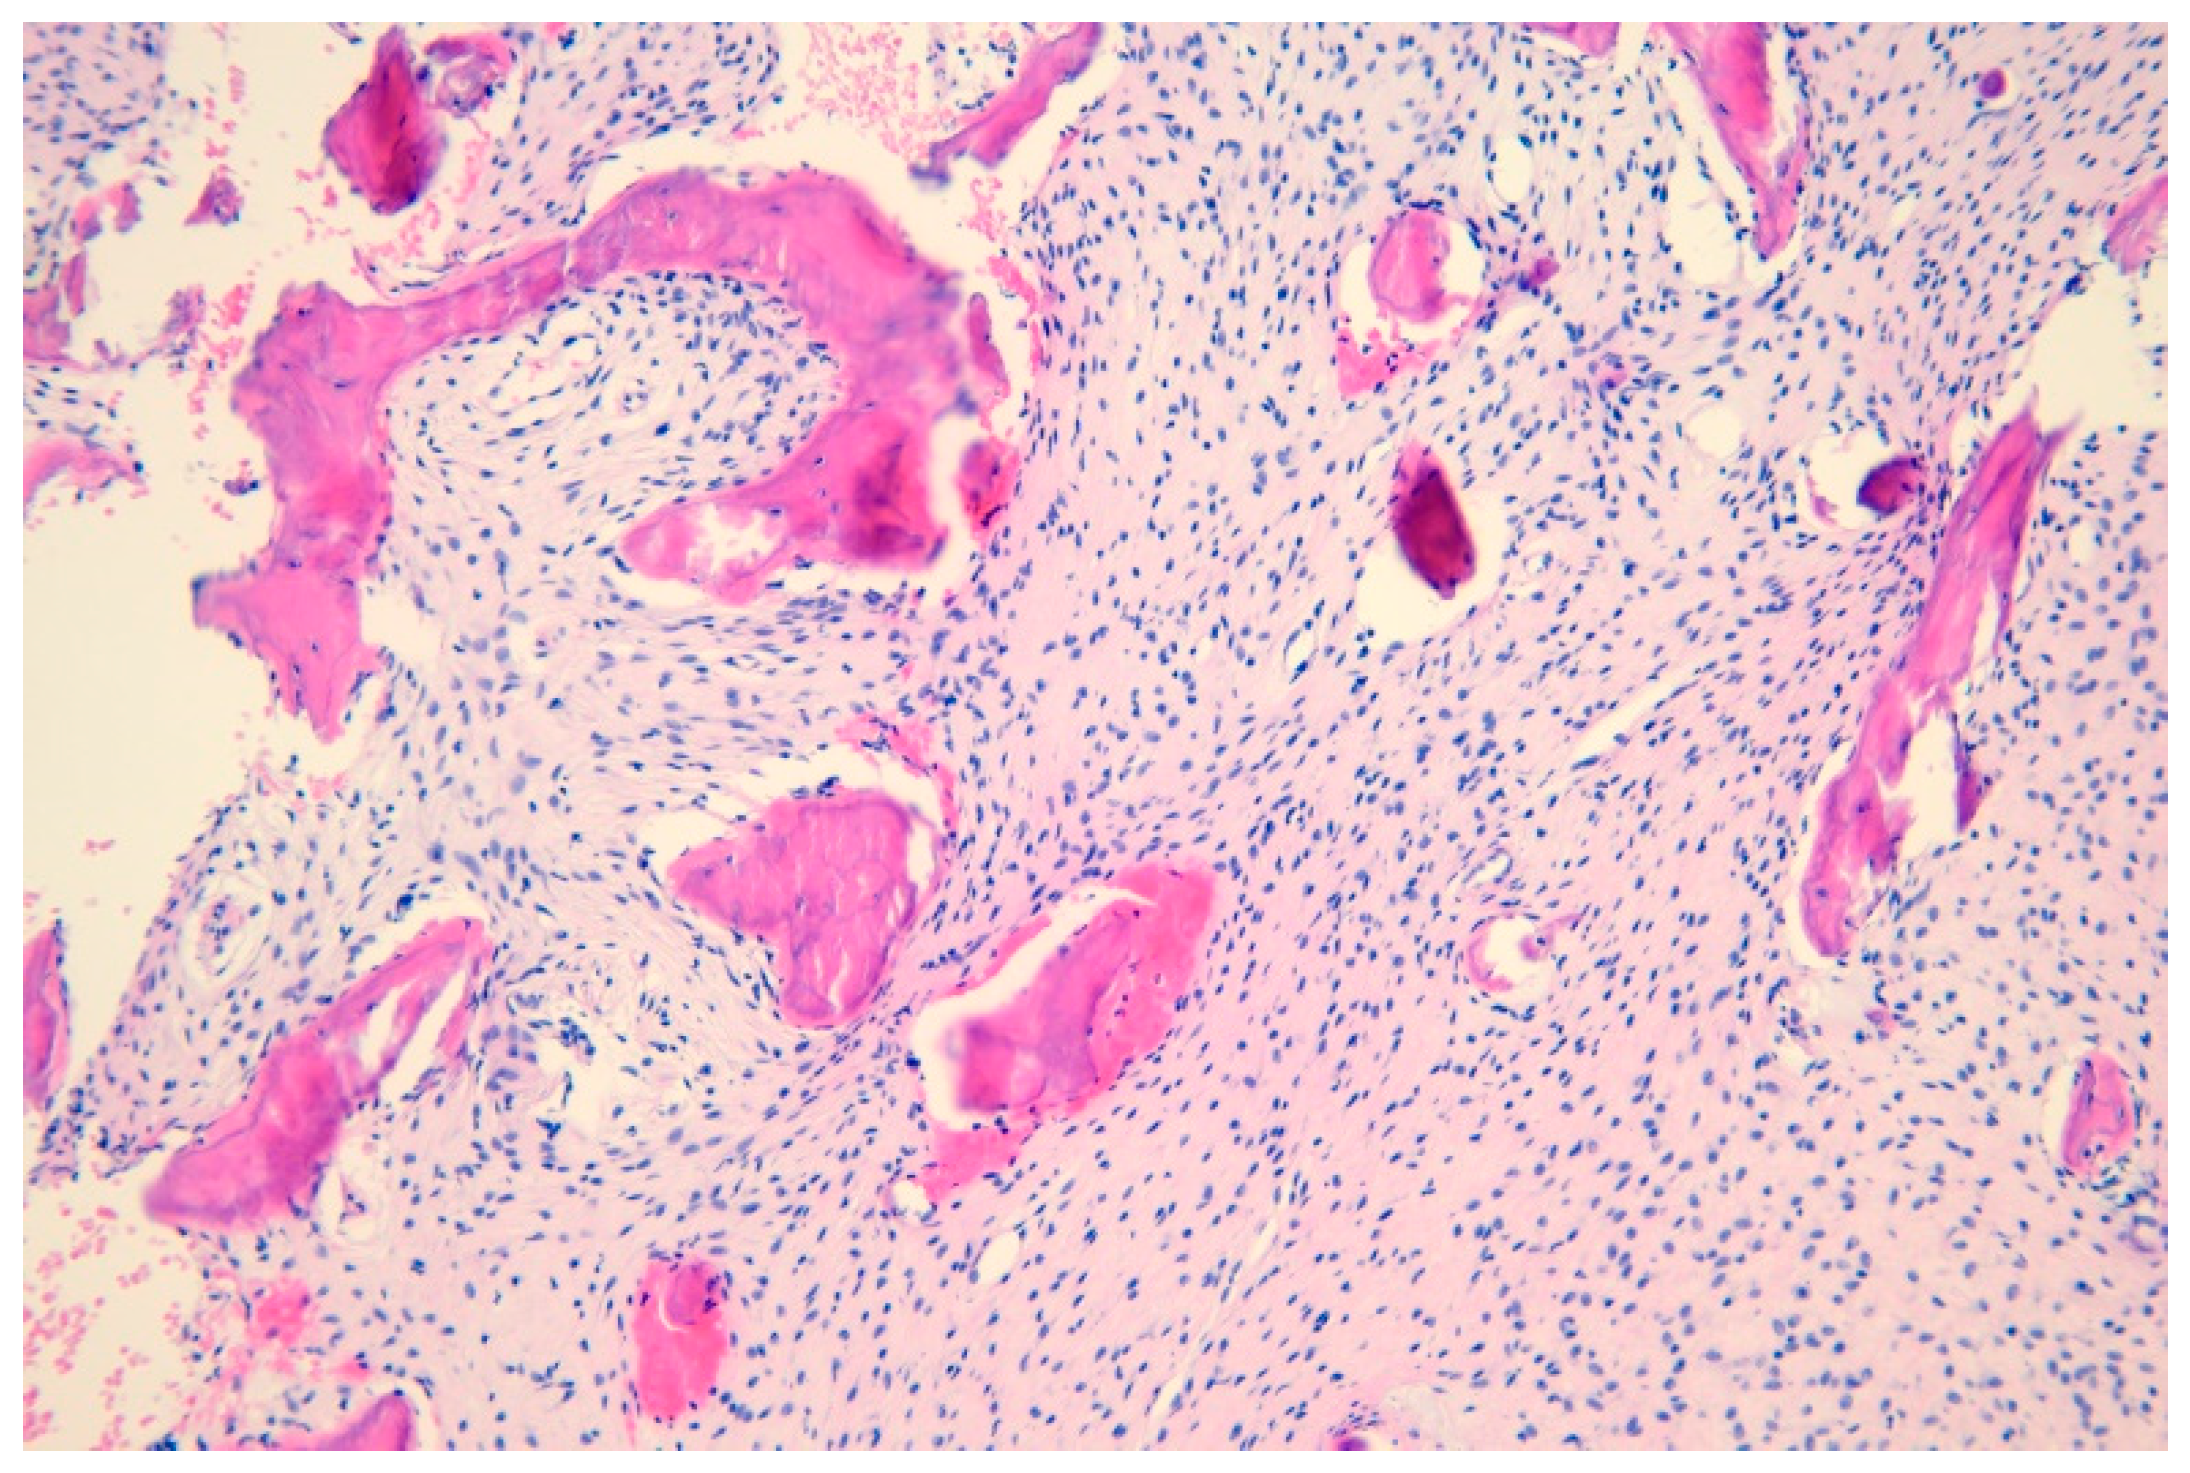

2. Case Description